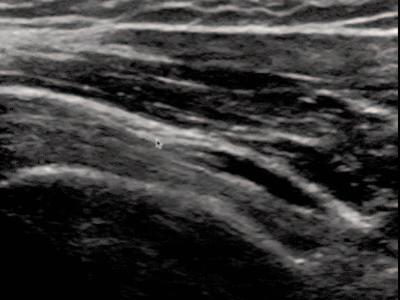

Figure 1a (left): Patient is seated with shoulder and elbow relaxed. Shoulder at 0 degrees of abduction, neutral rotation, elbow flexed and resting on leg or pillow with forearm supinated.

Transducer Placement: Short Axis (SAX). Probe placed transversely on the proximal anterior aspect of the shoulder, over the LHBT.

Figure 1b (right): Patient is seated with shoulder and elbow relaxed. Shoulder at 0 degrees of abduction, neutral rotation, elbow flexed and resting on leg or pillow with forearm supinated.

Transducer Placement: Long Axis View (LAX). Probe placed longitudinally on the proximal anterior aspect of the shoulder, over the LHBT.